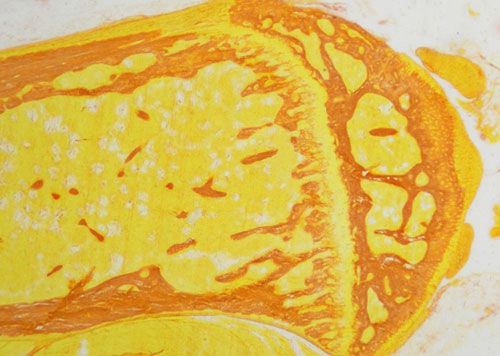

天狼猩紅和KWS都是強酸性染料,易與膠原分子中的堿性基團結合,吸附牢固。偏振光鏡檢查,膠原纖維有正的單軸雙折射光的屬性,與KWS-天狼猩紅結合,可增強雙折射,提高分辨率,從而區分兩型膠原纖維。未脫鈣骨組織切片經天狼猩紅染色后,普通光學顯微鏡下,膠原纖維呈紅色或鮮紅色,其他呈黃色;在偏振光顯微鏡下,Ⅰ型膠原纖維呈強橙黃色或亮紅色,Ⅲ型膠原纖維呈綠色。

實驗結果展示:

未脫鈣骨天狼猩紅染色